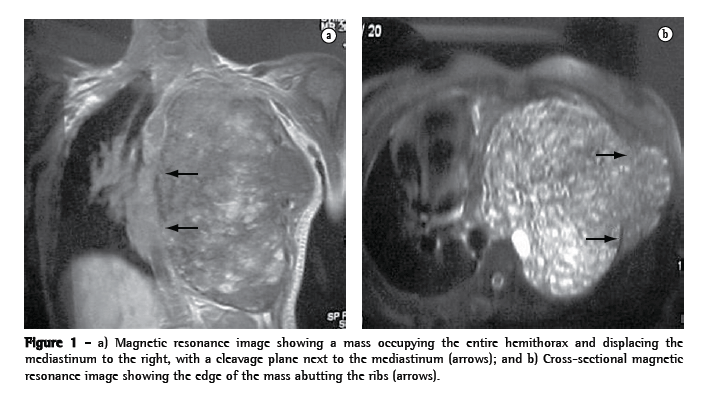

Magnetic resonance imaging of the chest revealed an extensive, mixed, and heterogeneous formation with well-defined borders. On T1-weighted images, a multiloculated mass appeared as a hyperintense signal corresponding to hemorrhagic foci and occupying the entire left hemithorax. This mass was compressing and displacing the mediastinal structures and the diaphragm. There was a small area of extrathoracic involvement at the level of the axillary line (Figure 1).

The results of the blood tests, including the determination of ionized calcium levels, were normal, as were the arterial blood gas analysis findings.